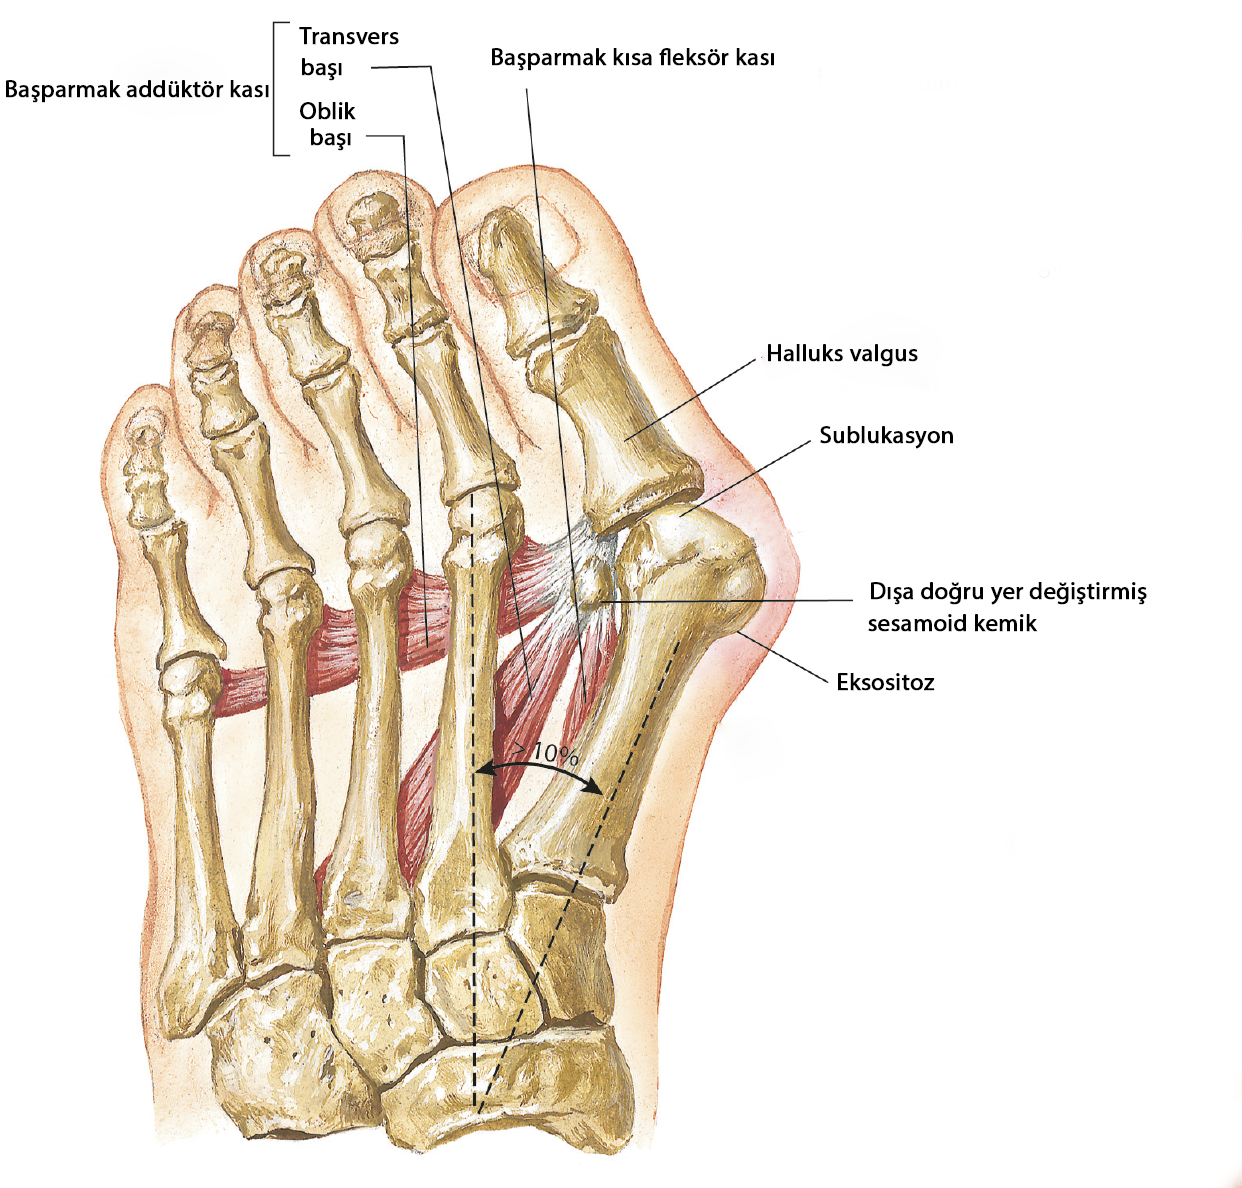

Asıl sorun birinci tarak kemiğinin ikinci ile arasının açılması ve birinci tarak kemiğinin içe doğru kaymasıdır.

Bu hastalıkta metatarsofalangeal eklemi oluşturan kemiklerin dizilimi bozulmuştur. Uzun metatarsal kemik ayağın iç kısmına doğru kayar ve ayak başparmağı açısındaki falanks kemikleri ikinci parmağa doğru kayar. MTP eklemi büyür ve ön ayağın iç kısmından dışarı çıkar.